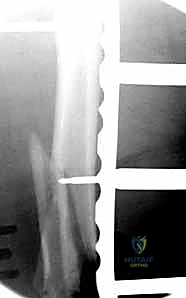

المرحلة الثانية: الفتح الجراحي والوصول للعظم

يستخدم الدكتور هطيف تقنيات الفتح الجراحي المحدود (Minimally Invasive Plate Osteosynthesis - MIPO) كلما أمكن ذلك، للحفاظ على التروية الدموية للعظم وتسريع الالتئام. يتم عمل شق جانبي بعناية للوصول إلى منطقة الكسر دون الإضرار بالعضلات المحيطة.

المرحلة الثالثة: إرجاع العظم (Reduction)

هذه هي الخطوة الأكثر أهمية. يقوم الدكتور هطيف بإعادة القطع العظمية المكسورة إلى مكانها التشريحي الأصلي. إذا كان الكسر ممتداً داخل المفصل، يتم تثبيت السطح المفصلي أولاً باستخدام مسامير دقيقة لضمان سطح أملس يمنع الاحتكاك والخشونة مستقبلاً.